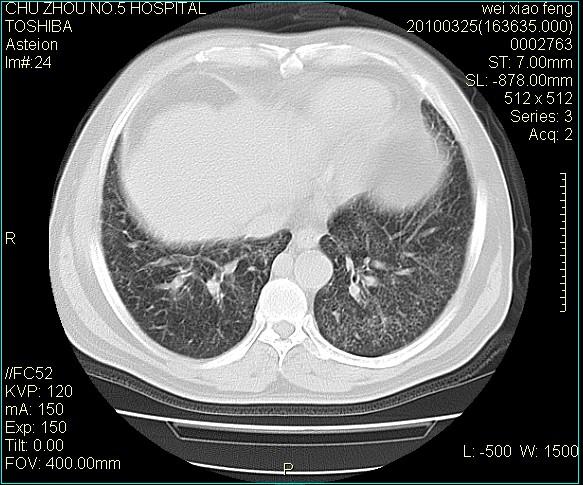

男,60岁,反复咳、痰、喘3月,加重3天。

双肺间质性改变。

考虑双肺血型潘散肺结核/

间质性肺炎伴间质纤维化!不排除伴有职业病!

急性血型潘散肺结核。

双肺间质纤维化,双肺血型潘散肺结核。

考虑间质性肺炎伴间质纤维化。

间质病变,间质炎症,间质纤维化趋势

右肺中叶结节影为原发灶,考虑右肺中叶周围型肺癌并淋巴道转移

间质性肺炎